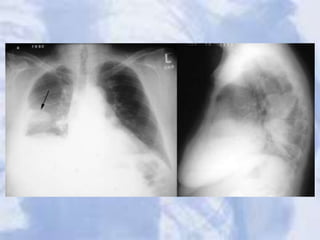

Pseudotumor: fluid has filled the minor fissure creating a density that

resembles a tumor (arrow). Recall that fluid and soft tissue are

indistinguishable on plain film. Further analysis, however, reveals a

classic pleural effusion in the right pleura. Note the right lateral gutter

is blunted and the right diaphram is obscurred.